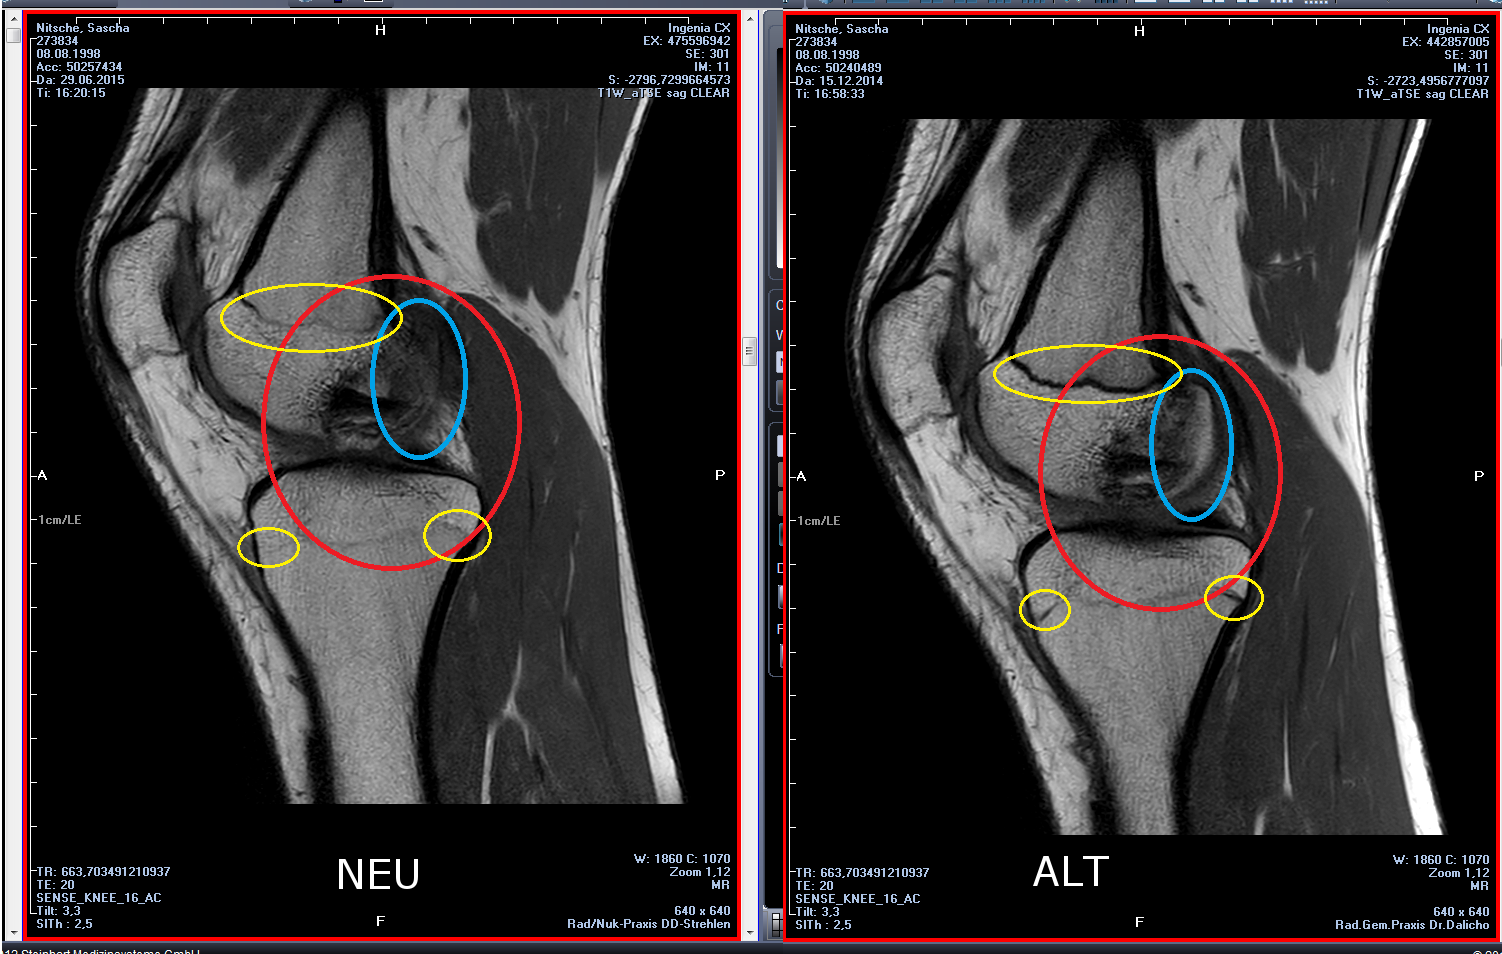

Die Erkrankung kann zufällig auf einem Röntgenbild entdeckt werden, das nach einem Unfall von der Knieregion, vom Sprunggelenk oder vom Ellbogen angefertigt wird. Bei typischen Beschwerden von aktiven Kindern und Jugendlichen kann mit einem solchen einfachen Röntgenbild die eindeutige Diagnose schon gestellt werden, weil der veränderte Knochen unterhalb der Gelenkoberfläche an typischer Stelle in der Oberschenkelrolle am Knie identifiziert werden kann. Manchmal kann eine sogenannte Tunnelaufnahme mit gebeugtem Knie die Schädigungszone noch besser zeigen. Zur genaueren Analyse sollte eine Kernspintomographie (MRT) durchgeführt werden. An den dabei erzeugten Bildern lässt sich die Lage und Größe des Befundes, die Tiefenausdehnung und vor allem eine Beteiligung des darüberliegenden Knorpels genau ausmessen. Es sind damit auch Aussagen zur Stabilität des Befundes zu treffen. Daraus ergeben sich dann entscheidende Anhaltspunkte für therapeutische Konsequenzen. Für die Verlaufsbeurteilung der Erkrankung eignet sich am besten das MRT, aber ggf. auch wieder die einfache Röntgenuntersuchung. Aufgrund der extrem hohen Kosten für das MR in den USA werden die Verläufe dort bis heute weitgehend nur mit Röntgenbildern dokumentiert, was zu eigenen Empfehlungen zur Verlaufsbeurteilungen führt. Generell wären aber die MR-Untersuchungen das Verfahren der Wahl. Sie erlauben eine differenzierte Beurteilung der unterschiedlichen Kriterien für Ausheilung, Instabilität und drohende Dissektion. Untersuchungen mit Sonographie können zuverlässige, aber nur orientierende Befunde am Femurkondylus erheben. Es ist damit zum Beispiel ein schneller, kostengünstiger und sicherer Ausschluss des Befalls auch der Gegenseite möglich.

Die Therapie der Osteochondrosis dissecans am Kniegelenk ist zunächst abhängig von der relativen Größe der Läsion im Vergleich zur Kondyle. Es gibt OCD an der medialen und an der lateralen Oberschenkelrolle (Kondyle). Selten kommt die Veränderung auch am Gleitlager gegenüber der Kniescheibe und an der Kniescheibe selber vor. Ein weiteres wichtiges Entscheidungskriterium ist das Stadium (stabil / instabil) der Läsion. Als Instabilitätszeichen tritt im MRT eine Zystenbildung, eine Vorwölbung des Knorpel-Knochen-Dissekates, ein Bruch der subchondralen Knochenlamelle und eine Rissbildung im Knorpel deutlich hervor. Ein wichtiges klinisches Symptom einer Instabilität des OD-Herdes ist eine Blockierung in der Gelenkfunktion, die als Zeichen der Beteiligung der Gelenkfläche an dem Erkrankungsprozess auftreten. Zusätzlich spielt das Alter des Patienten eine gewisse Rolle. Bei noch weit offenen Wachstumsfugen – also bei Jungen bis zum 14. und bei Mädchen bis zum 13. Lebensjahr – sind die spontanen Heilungsaussichten besser. Im Durchschnitt heilen bei allen Studien ca. 50 % der OCD-Fälle am Kniegelenk ohne operative Maßnahmen aus. Die komplette Ausheilung erfordert immer Monate bis Jahre, weil der notwendige Knochenumbau (Remodeling) durch Osteoklasten und Osteoblasten lange Zeit in Anspruch nimmt. Hierzu müssen ja knöcherne Strukturen aufgelöst, abtransportiert und wieder aufgebaut werden. Die therapeutischen Maßnahmen können aber je nach Fortgang der Heilung schon vor dessen komplettem Abschluss beendet werden.

Bei anhaltenden oder trotz konsequenter Sportpause zunehmenden Beschwerden am Knie oder Sprunggelenk, besonders bei Neuauftreten von mechanischen Symptomen wie Blockierungen und bei Größenzunahme oder Instabilitätshinweisen im MRT ist eine Gelenkspiegelung (Arthroskopie) des betreffenden Gelenkes empfohlen, um den Zustand des Gelenkknorpels beurteilen zu können, was mit der Kernspintomographie nicht zuverlässig gelingt. Harte Kriterien für eine Operation sind ein großer Herd, Zystenbildungen über 2,3 mm und Instabilitätszeichen im MR und natürlich sogar für eine notfallmässige Operation eine stattgehabte Dissektion (Lösung).

Je jünger der Patient ist, umso besser ist die Prognose der Heilung. Patienten nach dem Verschluss der Wachstumsfugen (je nach Geschlecht 15–17 Jahre) haben deutlich schlechtere Chancen für eine Heilung ohne Operation. Das Ziel der Behandlung ist eine vollständige Wiederherstellung der Struktur und Funktion des betroffenen Gelenks. Dazu ist eine Einheilung und eine Umstrukturierung (Remodeling) der veränderten Knochenareale Voraussetzung. Da Knochen generell (übrigens als einziges Gewebe des menschlichen Körpers) völlig narbenfrei und in physiologischer Struktur ausheilen kann und umbaut, sind primär keine anatomischen oder mechanischen Restschäden zu erwarten, solange die knorpelige Gelenkoberfläche nicht betroffen ist. Kleinere und stabile Befunde bei Jugendlichen können sich unter konsequenter Sportpause in frühestens einem Jahr spontan zurückbilden bzw. ausheilen. Bei größeren, ebenfalls stabilen, nicht dissezierten Befunden kann trotz operativer Maßnahmen (Anbohrung) die Heilung mehrere Jahre in Anspruch nehmen. Bei Stillstand der Heilung unter der konservativen Therapie ist eine Operation zu planen. Die Kriterien der Beurteilung lassen sich dazu nur zuverlässig im MR finden. Nach Ausheilung solcher Befunde sind die Ergebnisse meist als sehr gut und gut zu bezeichnen. Eine einmal ausgeheilte OD tritt nie erneut wieder auf: Der Grund ist die schon Jahre zurückliegende Genese als Durchblutungsstörung des Wachstumsknorpels, der zum Zeitpunkt der Ausheilung bereits vollständig in Knochen übergegangen ist.